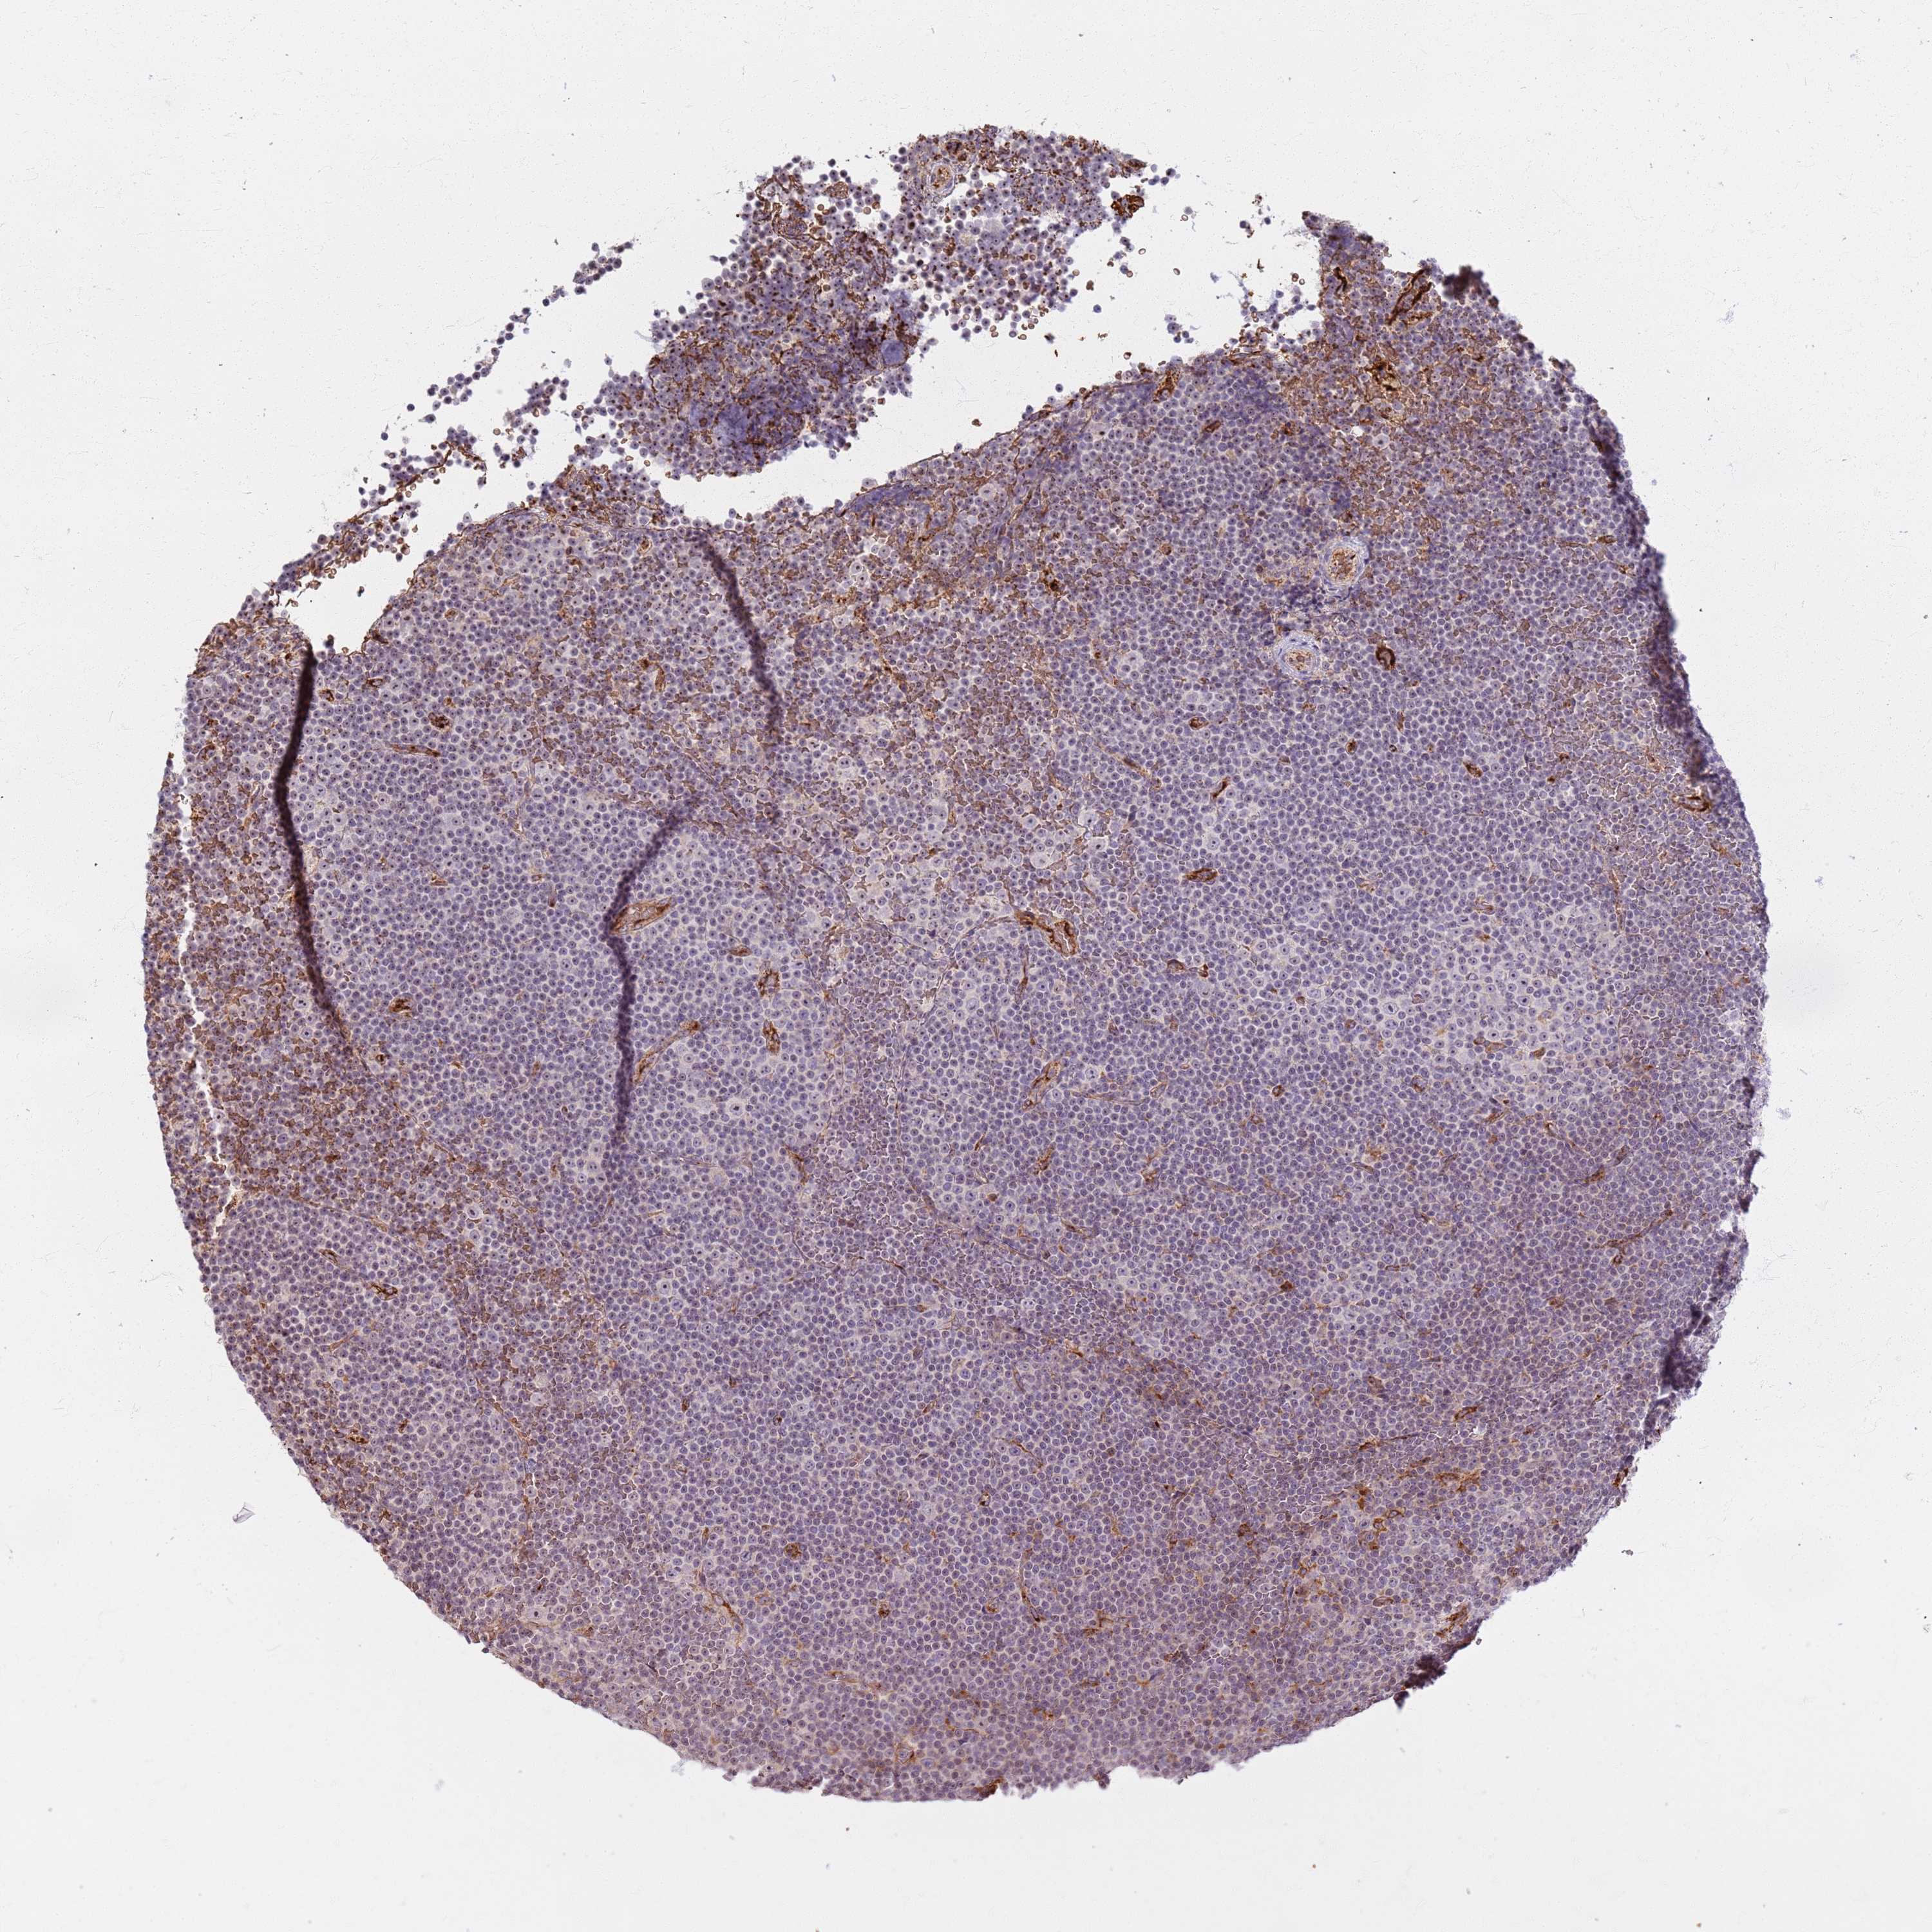

CANCER LYMPHOMA Show tissue menu

LYMPHOMA - Protein expressioni

A mouse-over function shows sample information and annotation data. Click on an image to view it in a full screen mode. Samples can be filtered based on level of antibody staining by selecting one or several of the following categories: high, medium, low and not detected. The assay and annotation is described here.

Each image is clickable and will lead to virtual microscopy that enables deeper exploration of all samples and also displays staining intensity scores, fraction scores and subcellular localization as well as patient and tissue information for each sample.

Antibody HPA043574

Hodgkin's disease, NOS

Malignant lymphoma, non-Hodgkin's type, High grade

Malignant lymphoma, non-Hodgkin's type, Low grade